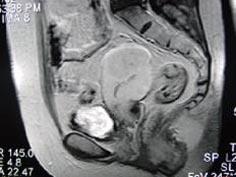

问题 55岁女性患者,绝经后阴道排液半年余,行MRI检查,如图所示,最佳答案是 ( )

选项 A、子宫肌瘤 B、子宫内膜癌 C、子宫颈癌 D、正常子宫 E、子宫内膜异位症

答案 B